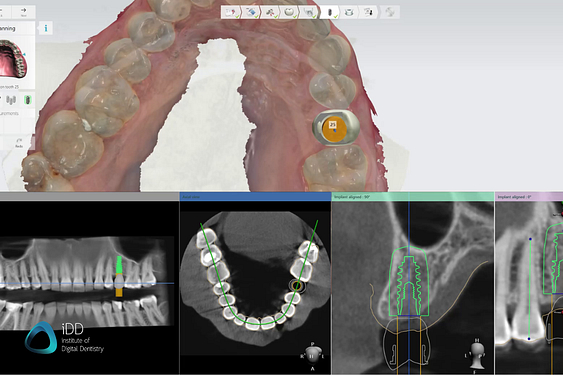

This uses 3D imaging and planning software and a printed surgical guide to provide the dentist with a virtual map of where to place the implants.

For a restorative-driven workflow, a digital tooth mock-up is used to help find the most aesthetic and functional implant position. CBCT data help you account for bone density, sinus, or inferior alveolar nerve.

The surgical guide design is very straightforward and fully customizable, windows are added to help assess proper seating in the patient’s mouth.